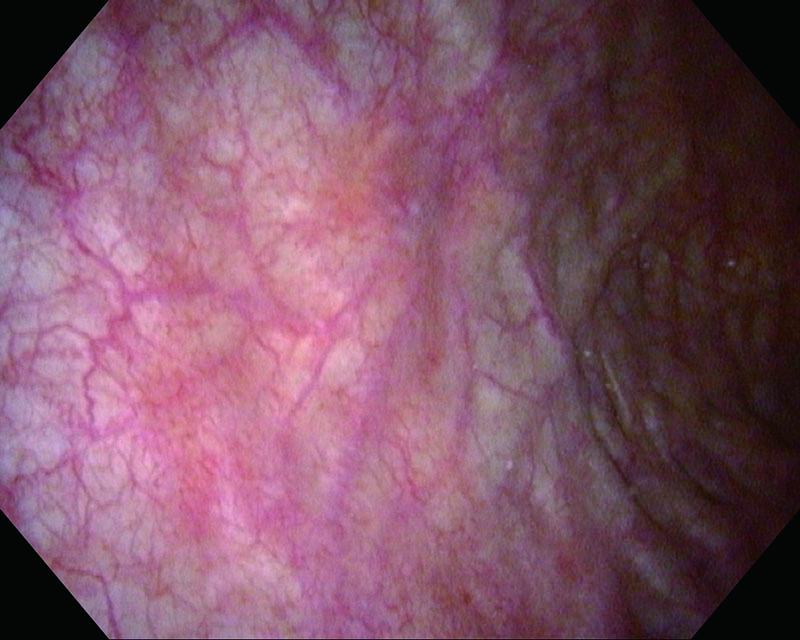

発赤 81歳・男性

通常光

NBI

病理 UC, CIS

コメント

膀胱粘膜の発赤・不整像を認め、上皮内がんを疑う症例。